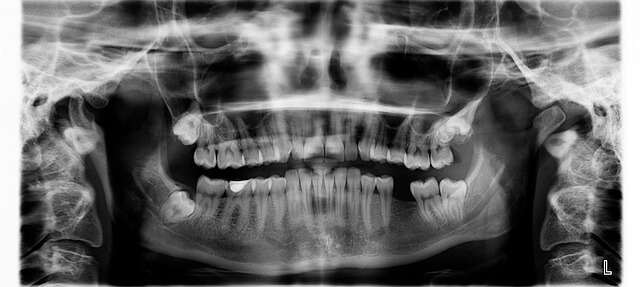

*임플란트 시술과정 시술순서를 처음 접하면 복잡하게 느껴질 수 있어요. 제가 직접 사용해보니 첫 단계는 철저한 정밀 검사입니다. 구강 상태를 꼼꼼히 확인하고 뼈가 충분한지, 신경 위치는 괜찮은지 파악하는 과정이에요. *이 검사 덕분에 시술 전체가 안전하게 계획돼서 불안감이 줄더라고요.

*임플란트 시술기간은 대개 3~4개월이 걸리며, 개인별 건강 상태와 잇몸 뼈의 조건에 따라 다르게 나타날 수 있습니다. 제가 직접 사용해보니, 임플란트 시술과정은 크게 정밀 검사, 1차 수*, 안정화 기간, 2차 수*, 보철물 장착의 순서로 진행됩니다. *이 과정에서 최장 기간을 차지하는 안정화 기간이 시술완성에 중요한 역할을 합니다.